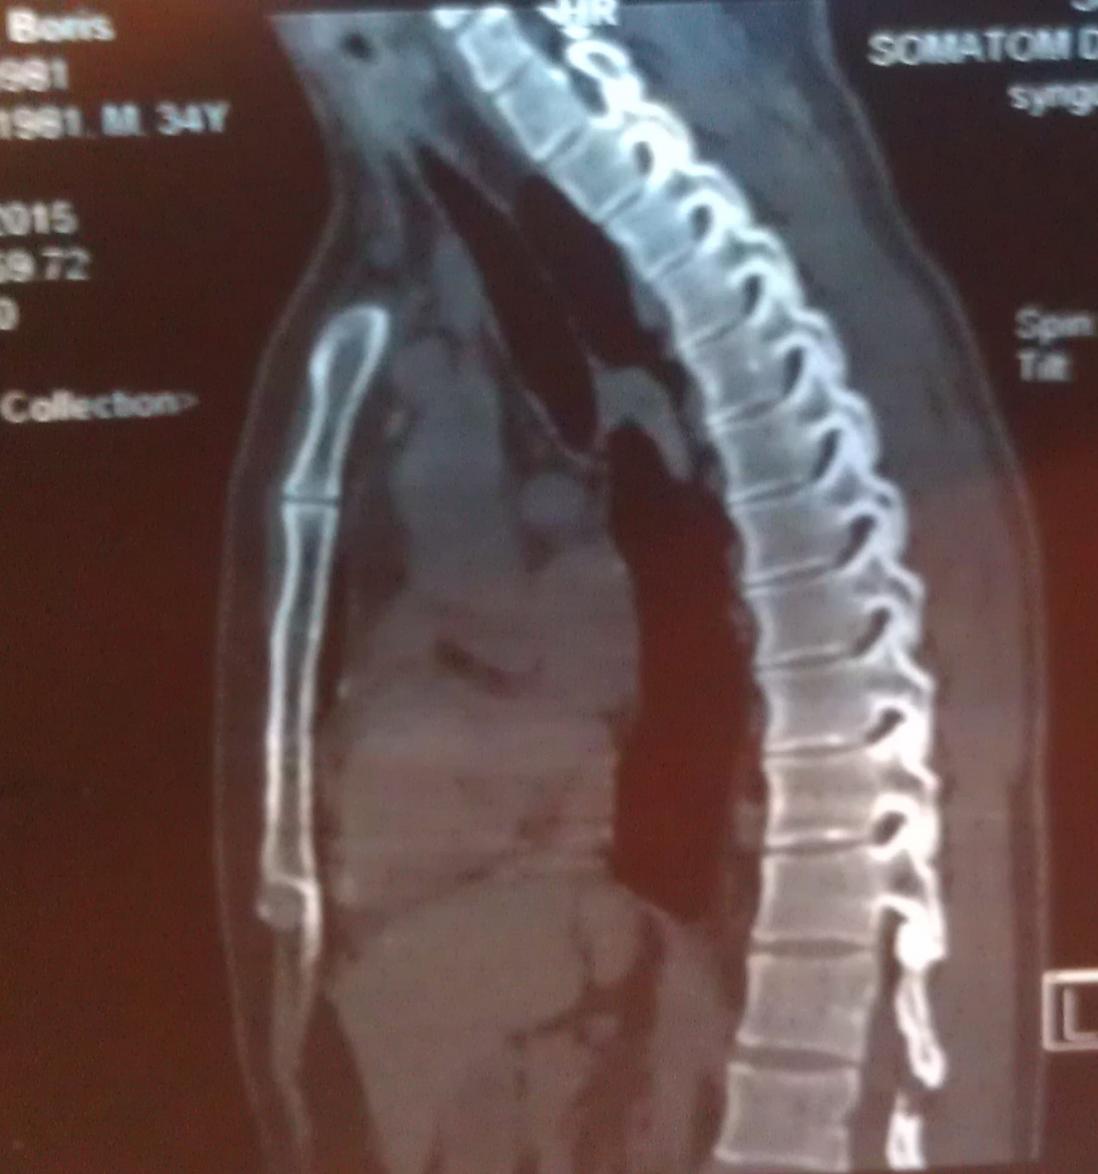

А достаточно ли плохих ревмопроб и компьютерной томограммы, где виден кифоз - чтобы поставить диагноз "болезнь Бехтерева"?

Вот моя компьютерная томограмма позвоночника.

Нажмите на изображение для увеличения

Название: 1 - компьютерная томограмма позвоночник, грудной отдел.jpg

Просмотров: 1600

Размер:	83.2 Кб

ID:	1182Нажмите на изображение для увеличения

Название: 3 - компьютерная томограмма на болезнь Бехтерева.jpg

Просмотров: 1596

Размер:	92.7 Кб

ID:	1184Нажмите на изображение для увеличения

Название: 4 - Снимок позвоночника.jpg

Просмотров: 1571

Размер:	85.8 Кб

ID:	1185Нажмите на изображение для увеличения

Название: 5 - позвоночник при остеохондрозе.jpg

Просмотров: 1628

Размер:	91.0 Кб

ID:	1186Нажмите на изображение для увеличения

Название: 2 - компьютерная томограмма позвоночник.jpg

Просмотров: 1610

Размер:	95.5 Кб

ID:	1183

Судя по снимкам ярко выраженный кифоз, отсюда и сдавливание легких Плохо видно, вроде срастания позвонков нет и это очень хорошо, На данном этапе желательно следить за своим прямохождением-прямосидением и упражнениями способствующими этому.Не ходить к костоломам, ну вроде как потянем-растянем-подстукнем и тд.